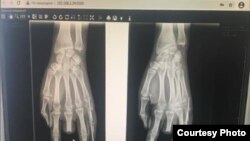

«Баарынан жаманы, ошол күнү "Тез жардам" чакырганда келген медкызматкерлер кантип жардам көрсөтүүнү билбей коюшкан. Ооруканага алып барышканда гана аты жогу менен чыпалакты чогуу тигип, гипс салышкан. Ортоңку манжасы толук түшүп, ал жерден кан фонтандай эле атып турган».

Жакында эле Гулянын колуна операция жасалып, Илизаров аппараты коюлду. Аны апрелдин орто ченинде алышат. Ал эми кесилген манжанын ордуна жасалма бионикалык манжа тагуу зарыл. Абдиеванын айтымында, андай жасалма манжа бери дегенде 1,5 миллион рубль турат.